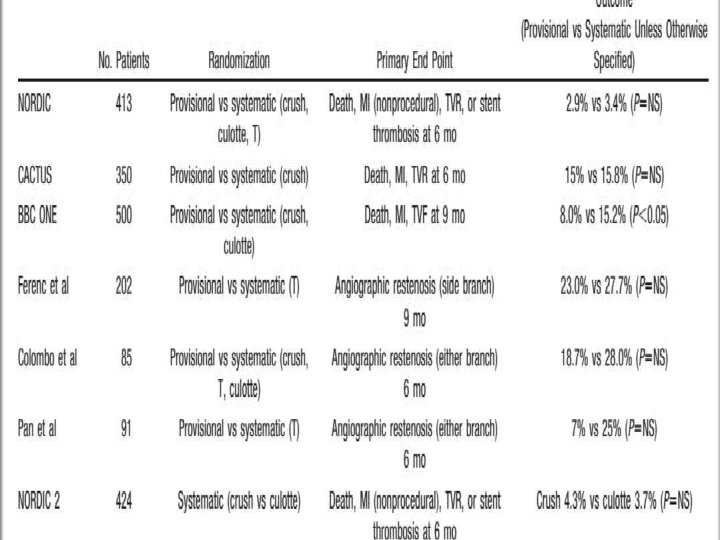

One vs two stents • • • Important trials NORDIC 2 BBC CACTUS

1. Nordic I: provisional T stenting as good as systematic side branch stenting 2. Nordic II: Culotte better than Crush 3. Cactus: provisional T stenting not worse than crush 4. BBC ONE: step wise approach with provisional T stenting better than initial complex procedures 5. Bad Krozingen: no difference provisional vs systematic T 6. Double Kiss Crush Study: DK Crush better than conv. crush Steigen Circulation 2006; 114: 1955; Erglis TCT 2008; Hildick-Smith TCT 200 Ferenc EHJ 2009; Chen JInterv Cardiol 2009; 22: 121 -27